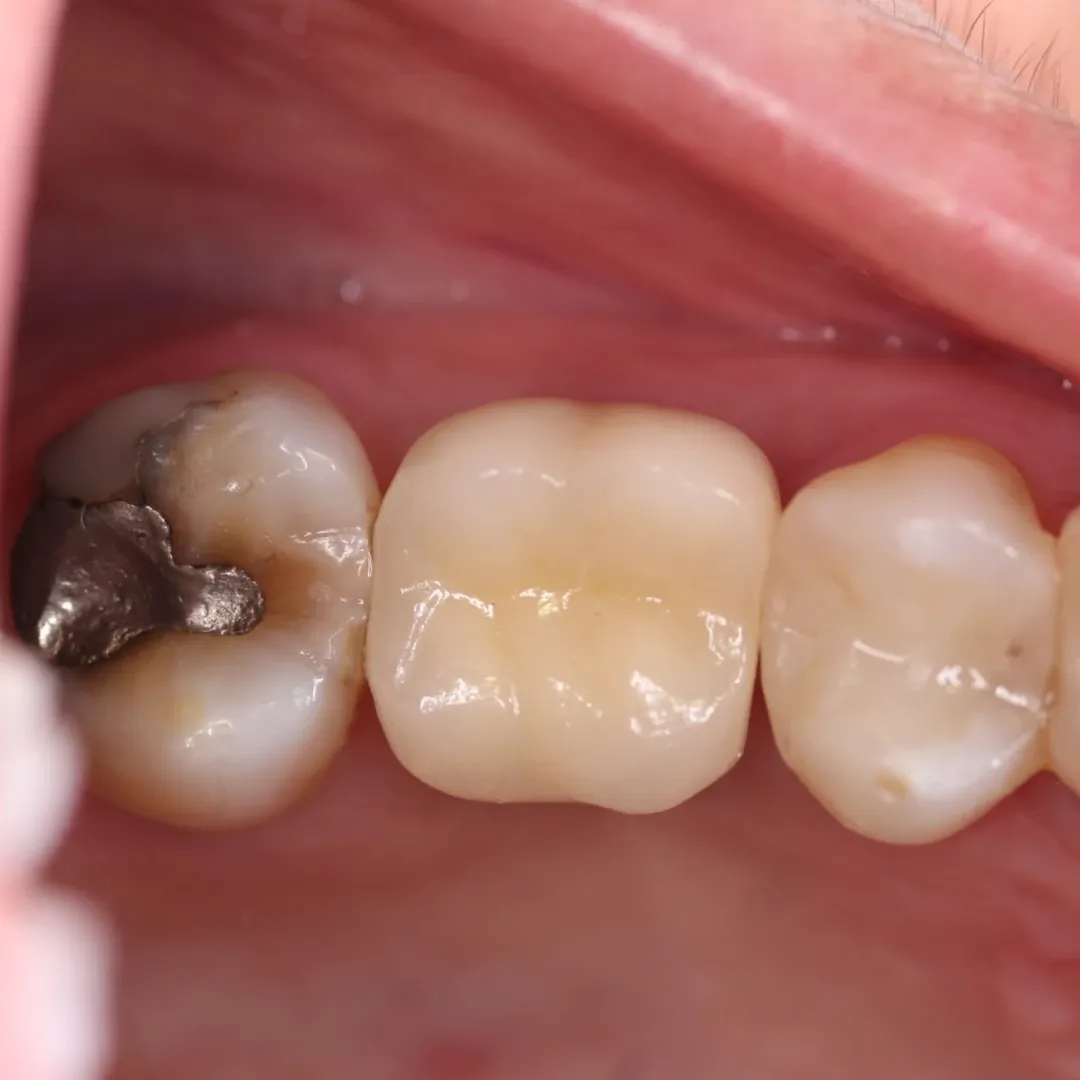

Hoje, compartilho um caso que exemplifica bem essa abordagem integradora: a reabilitação com prótese cimentada sobre munhão universal Neodent, destacando os resultados obtidos no perfil gengival após o uso de provisório para condicionamento tecidual.